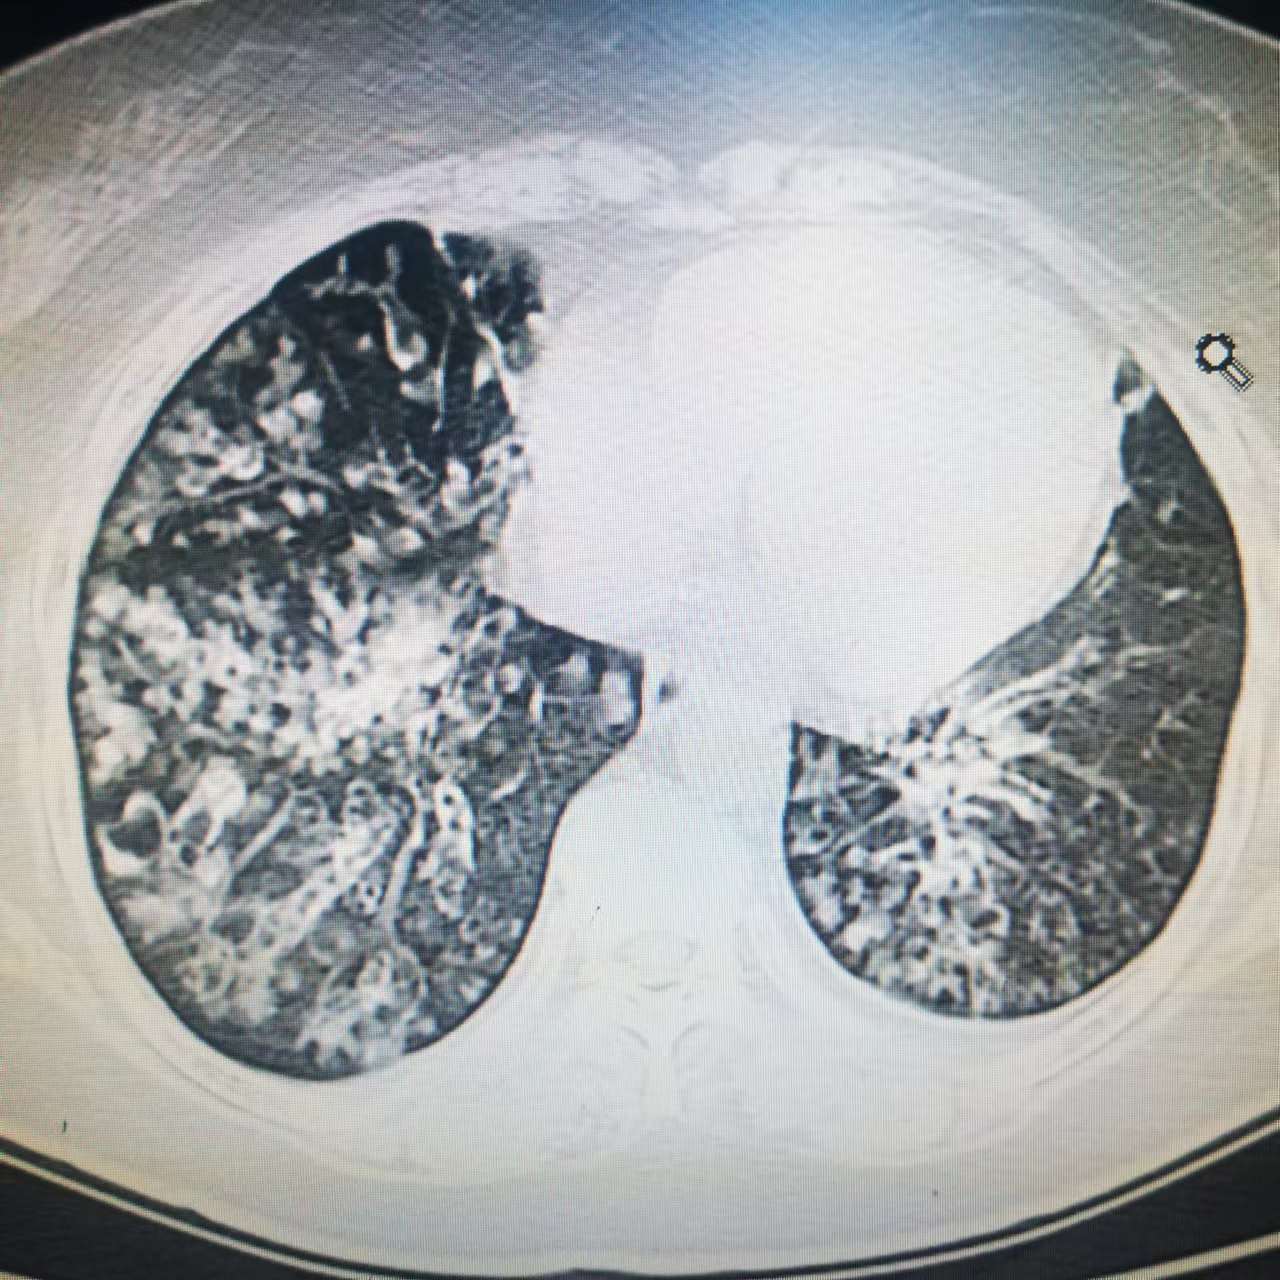

“我老是咳嗽咳痰,做了肺CT,說(shuō)是支氣管擴(kuò)張,這是什么病呀?嚴(yán)不嚴(yán)重?”呼吸科門(mén)診經(jīng)常遇見(jiàn)拿著片子憂心忡忡的支擴(kuò)患者。其實(shí)支氣管擴(kuò)張?jiān)谂R床中很常見(jiàn),但是常常被人忽視,往往出現(xiàn)咯大量膿痰、咯血、發(fā)熱才來(lái)治療,肺結(jié)構(gòu)破壞已經(jīng)比較嚴(yán)重了。所以,讓大眾認(rèn)識(shí)支擴(kuò)、了解支擴(kuò)就顯得尤為重要!一、什么是支擴(kuò)?我們的肺像一棵倒過(guò)來(lái)的樹(shù),主干是氣管,往下逐漸越分越細(xì),直到連接到肺泡,就如同樹(shù)枝連著樹(shù)葉。支擴(kuò),全稱(chēng)為支氣管擴(kuò)張癥,就是支氣管異常擴(kuò)張了,本來(lái)應(yīng)該變細(xì)的氣管因?yàn)檠装Y增粗變形了。有人會(huì)問(wèn),氣道增粗了,不是更通暢了嗎?其實(shí)不然,變粗是因慢性炎癥反復(fù)刺激造成的結(jié)構(gòu)破壞,氣道管腔狹窄變形,粘液分泌增加,伴行血管受損出血,長(zhǎng)期則造成自身免疫功能的低下,就是反復(fù)感染,病情纏綿難愈、逐漸加重。二、支擴(kuò)是怎么形成的??西醫(yī)認(rèn)識(shí)支擴(kuò)可分為先天性與繼發(fā)性兩種。先天性支擴(kuò)主要是遺傳或發(fā)育缺陷導(dǎo)致;繼發(fā)性支擴(kuò)在我們國(guó)家更常見(jiàn),幼年反復(fù)發(fā)生的肺炎、百日咳、支原體、病毒感染(麻疹病毒等)造成的管壁破壞及結(jié)構(gòu)變形,青年時(shí)期感染結(jié)核造成的瘢痕牽拉變形,成年后沒(méi)有及時(shí)有效治療的肺部感染是形成支擴(kuò)最常見(jiàn)的因素。往往是由于支氣管感染和阻塞,兩者相互影響,形成惡性循環(huán)。?中醫(yī)認(rèn)識(shí)支擴(kuò)屬于中醫(yī)的“肺癰”、“內(nèi)傷咳嗽”范疇,其病位在肺,痰濁、瘀血、熱邪是常見(jiàn)的致病因素,正虛邪戀、肺絡(luò)損傷是其主要病機(jī),病性往往虛實(shí)夾雜。若患病日久、病情逐漸加重。三、支擴(kuò)的癥狀和危害??支擴(kuò)的癥狀?咳嗽、咯痰是支氣管擴(kuò)張癥最常見(jiàn)的癥狀,超過(guò)90%的病人有長(zhǎng)期的慢性咳嗽,且一般咯痰量較多。支擴(kuò)的痰液可為黏液性、黏液膿性或膿性。合并感染時(shí)咳嗽咳痰量明顯增多,可呈黃綠色膿痰,重癥患者痰量可達(dá)每日幾百毫升。半數(shù)患者可出現(xiàn)不同程度的咯血,咯血可從痰中帶血至大量咯血,嚴(yán)重咯血可能會(huì)造成窒息,甚至危及生命,所以大量咯血時(shí)一定要高度重視、及時(shí)就醫(yī)。?支擴(kuò)有什么特殊體征?肺部固定的濕啰音是支氣管擴(kuò)張癥的特征性表現(xiàn),這種濕啰音往往在處于緩解期時(shí)也能聽(tīng)到,當(dāng)然感染發(fā)生時(shí)濕啰音會(huì)明顯增多。還有些病人可以見(jiàn)到杵狀指(趾)。四、支擴(kuò)的診斷n??如果您有反復(fù)咳嗽、咯痰或咯血表現(xiàn),可以來(lái)醫(yī)院進(jìn)行檢查。診斷其實(shí)并不難,胸部高分辨CT就可以發(fā)現(xiàn),它是臨床診斷支氣管擴(kuò)張癥的主要方法。五、得了支擴(kuò),我們?cè)撊绾伪Wo(hù)肺?確診了支擴(kuò)怎么辦?別擔(dān)心,讓我們一起好好保護(hù)它。利用中醫(yī)“治未病”的思想,未病先防,已病防變。?預(yù)防為主預(yù)防支擴(kuò)的關(guān)鍵就是預(yù)防呼吸系統(tǒng)的感染,感染在支氣管擴(kuò)張癥中扮演了重要的角色,盡早控制呼吸道的感染,積極接種麻疹、百日咳疫苗,預(yù)防、治療肺結(jié)核,以防患于未然。同時(shí),清淡而有營(yíng)養(yǎng)的飲食,多飲溫水,多曬太熱,鍛煉身體,呼吸新鮮空氣,都可以提高免疫力,減少感染的發(fā)生。?已病防變已患支擴(kuò)的病友需要注意以下方面:⑴天冷應(yīng)注意保暖,避免受涼感冒,多數(shù)感冒往往是導(dǎo)致支擴(kuò)急性加重的重要誘因。⑵堅(jiān)持進(jìn)行體位引流,就是想辦法通過(guò)改變身體的姿勢(shì)和體位,把氣管和肺內(nèi)的痰液“倒”出來(lái),例如支氣管擴(kuò)張的部位在下葉的,就采取頭低腳高勢(shì),可以跪在床上一段時(shí)間,每次約5-10分鐘,每天應(yīng)該做2-3次。⑶咯血時(shí)應(yīng)輕輕將血咳出,坐起來(lái)、臉朝下,切忌屏住咳嗽以免形成窒息。有的人怕咳嗽而不敢咳,認(rèn)為一咳嗽就會(huì)繼續(xù)出血,這是不對(duì)的。因?yàn)闅獾赖某鲅豢瘸鰜?lái)即會(huì)阻塞氣道,反而危險(xiǎn)。⑷食療:飲食忌油膩、煎炸食品,少食辛辣刺激的食物可以配合百合、山藥等食物食療。⑸心情平和,忌惱怒。⑹注意休息,忌勞倦。??支擴(kuò)的自我調(diào)養(yǎng)⑴??療:飲食上以質(zhì)地清淡、營(yíng)養(yǎng)豐富的食物為主,例如小米、豆腐、白菜、白蘿卜、胡蘿卜、桃、葡萄、蘋(píng)果、銀耳、百合、荸薺、杏仁等,慎食或禁食辛辣刺激食品,忌煙忌酒,忌食辛燥發(fā)物等。⑵營(yíng)養(yǎng)支持:對(duì)支擴(kuò)患者,可加用潤(rùn)肺補(bǔ)腎之品以增強(qiáng)機(jī)體抗病能力。支擴(kuò)病人痰量較多,易耗津波,故適量多飲水,可補(bǔ)充體內(nèi)消耗的律液。適量補(bǔ)充營(yíng)養(yǎng)食品,如含有優(yōu)質(zhì)蛋白、維生素C的食品,改善營(yíng)養(yǎng)狀況,提高機(jī)體免疫力。⑶保持大便通暢:中醫(yī)認(rèn)為“肺與大腸相表里”,大便通暢對(duì)防治支擴(kuò)繼發(fā)感染具有重要作用。平素服些潤(rùn)腸通便之食品,如白蘿卜、血豆腐、大白菜等既可通便,又可化痰。多吃蔬菜水果,如生梨、香蕉等。⑷宜忌:發(fā)病期間忌食溫燥食品,如羊肉、狗肉、豬頭肉、海膽、油膩之品,慎食或禁食辛辣等刺激性食品;忌煙,忌酒,避免煙霧刺激及濕熱內(nèi)蘊(yùn);忌急躁發(fā)怒郁悶,以避免肝郁化火、木火刑金而導(dǎo)致支擴(kuò)加重;慎起居,避風(fēng)寒,避免外感誘因;適量運(yùn)動(dòng),恢復(fù)改善心肺功能,增強(qiáng)機(jī)體免疫力。最后,讓我們醫(yī)患攜手保護(hù)好我們的肺,能夠順暢呼吸、健康生活!????????????????????????????何沂?樊茂蓉??苗青